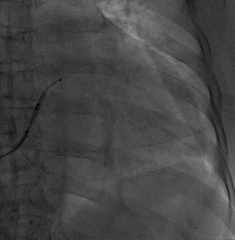

AP

LAO45

RAO30

固定左室电极,连接CRTD(DTBC2QQ),手术最终影像